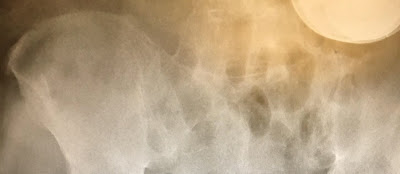

An angry lady who felt used and dumped by his lover after he cheated on her with other women, has taken her revenge mission to a whole new level by inserting screws into his p*nis According to a shocking story and photo posted on Reddit which has already gone viral online and on social media, a man passed out and his estranged angry girlfriend who felt he had cheated and dumped her, reportedly shoved nine screws inside his urethra.

According to a Reddit poster, the man had broken up with the girl after she accused him of cheating. In retaliation she got him drunk and when he passed out, she inserted the screws one after the other inside his urethra.

"A man was rushed to the hospital – with nine screws inside his urethra. Police claim that the man’s estranged girlfriend is responsible for “putting the screws” to her ex.

"Online reports say that the man broke up with his GF, who he had been seeing for three years – and she was upset. So she got him drunk, and when he passed out she inserted the screws one after the other inside his urethra."

See the graphic photo below;